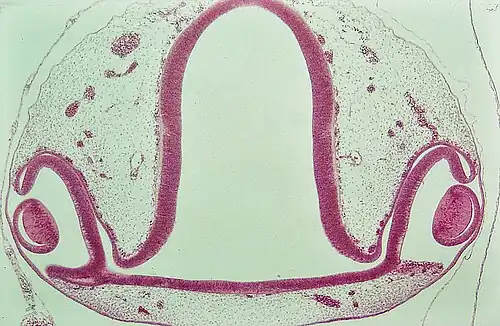

Oogbeker met lensaanleg. Kippenembryo (H&E-kleuring)

Het is een structuur die bestaat uit een binnenste en een buitenste laag, die eindigt in de optische steel. De buitenste laag wordt het retinaal pigmentepitheel, de binnenste laag wordt het neurosensorische netvlies, terwijl de optische steel geleidelijk wordt gekoloniseerd door zenuwen geproduceerd door zenuwknoopcellen voor het vormen van de oogzenuw. Daar waar de binnenste laag van de oogbeker over gaat in de buitenste laag is de rand van de pupil en zal zich uiteindelijk ontwikkelen tot de iris. De optische steel vormt de oogzenuw (nervus opticus).